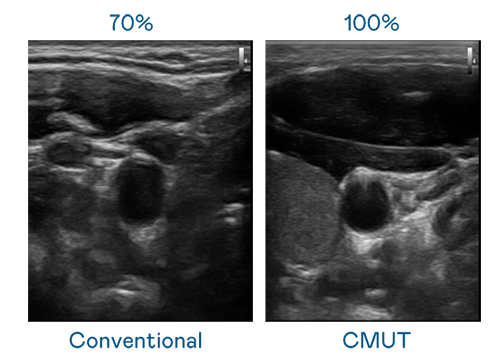

CMUT 技术是一种用电容式微机电元件来产生超音波讯号的技术。与传统 PZT 压电式技术相比,CMUT 频宽增加 30%,更宽频的超音波讯号让影像解析度大幅提升,是实现高影像品质医疗超音波扫描、促进精准医疗发展的关键技术。

大频宽带来超清晰影像

超音波影像的解析度高低,首先取决于探头能发出的讯号频宽。巅峰国际 CMUT 可提供高清晰的超音波讯号,提供高频宽、高灵敏度、影像纹理细节更高的超音波影像,协助医护人员缩短影像判读时间及利用精准的医疗影像进行诊断。